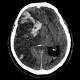

After a massive stroke, 45-year-old mom makes 5K debut

lehighvalleylive.com On Sunday, she’ll continue her path to recovery by running her first race in the Lehigh Valley since the stroke, competing in the West End St. Patrick’s Day 5K in Allentown. She plans to run every step, something she could’t do before her stroke. “I am … |